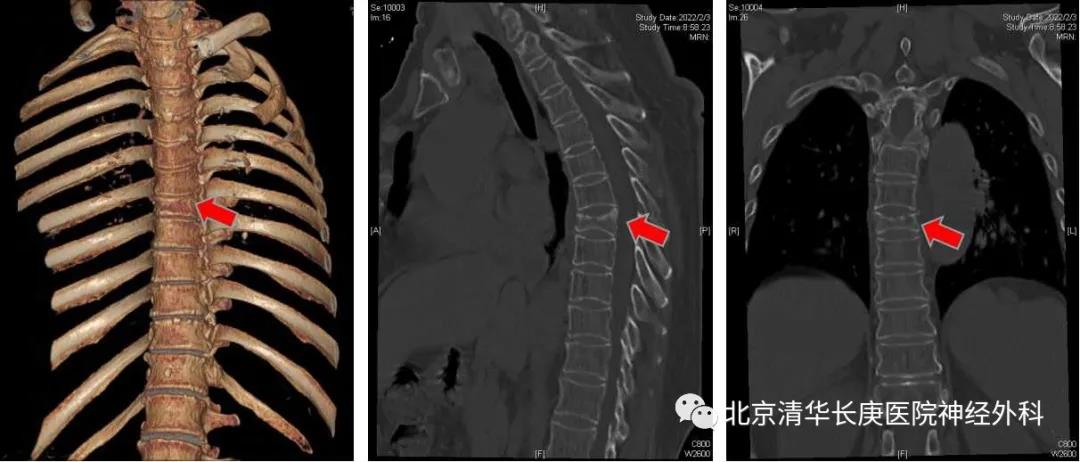

我院神经外科今天就为一名摔伤后椎体压缩骨折的病人进行了术中O-arm三维影像引导下的微创经皮穿刺椎体成形术。病人是一名65岁女性,摔伤后有严重的胸背部疼痛,伴腹部的局部放射,术前检查提示为胸7椎体压缩骨折。

图1 术前CT提示T7椎体严重压缩